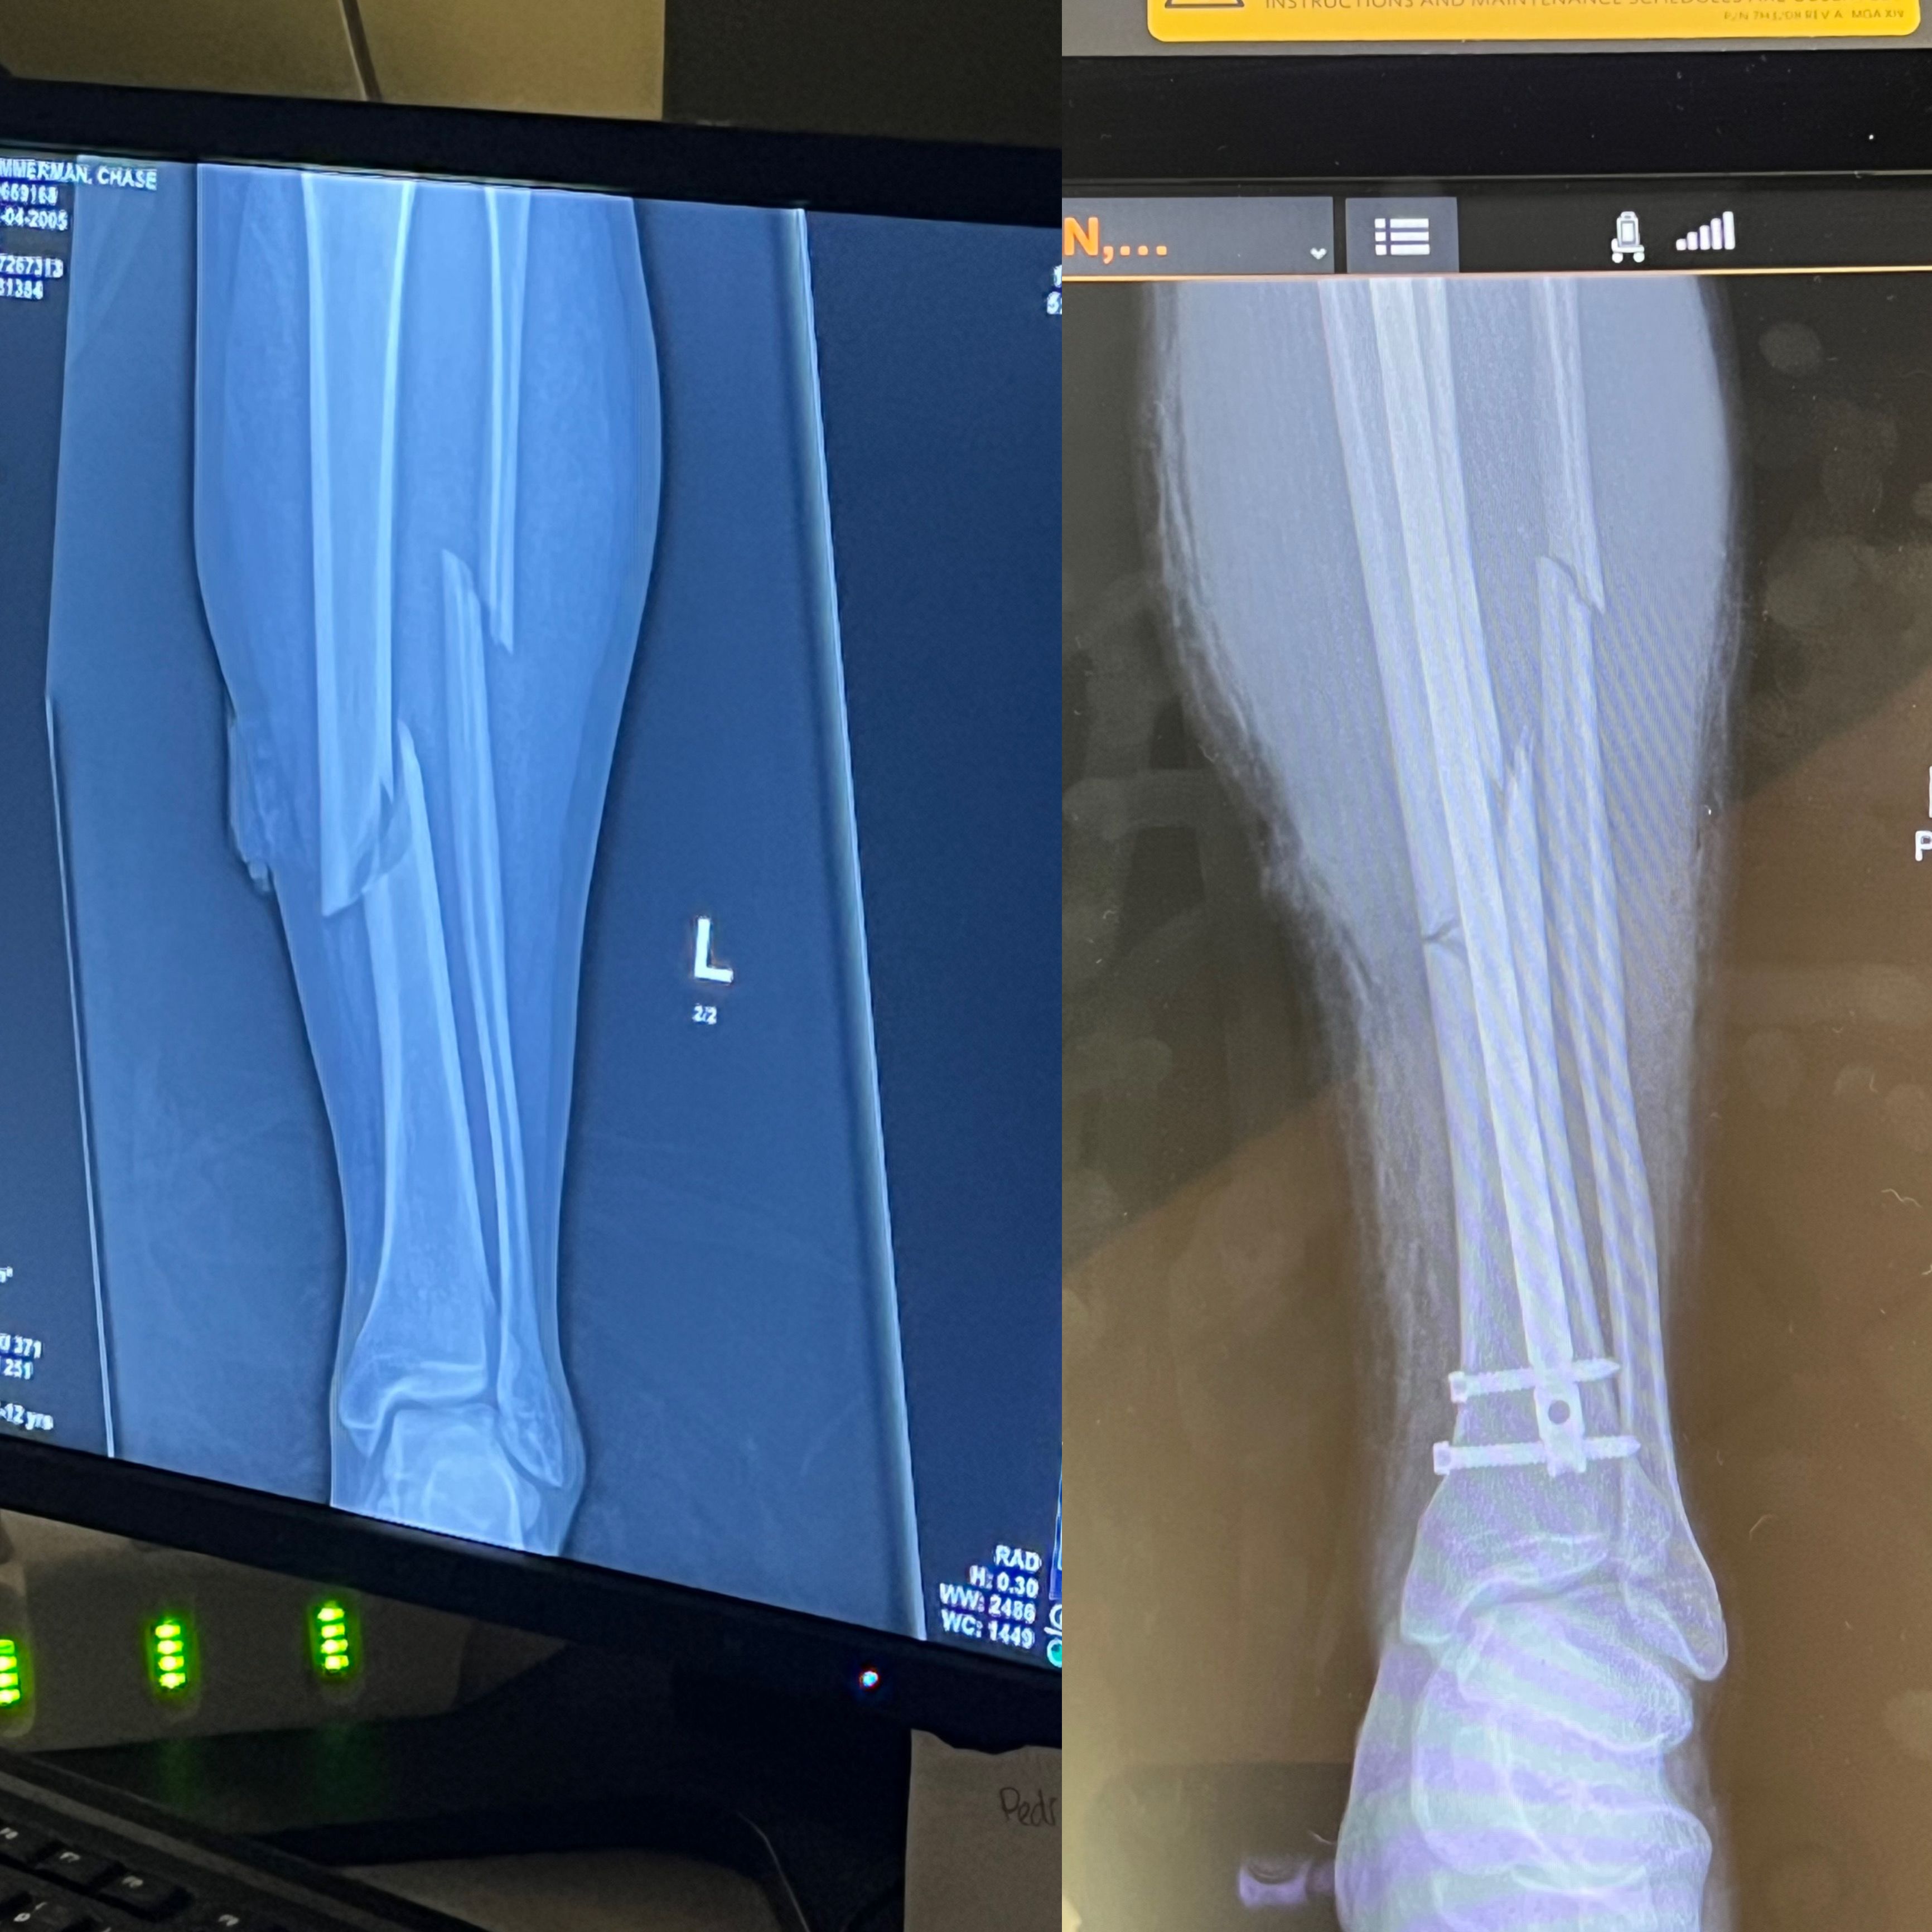

In fact, he had suffered a compound tibia fibula fracture.

“I looked down, and I was kind of holding my leg, and it was like, dangling in half,” he said. “So I knew it was a pretty brutal injury.”

X-rays of Chase Zimmerman's Compound Tibia Fibula Fracture (Courtesy of Chase Zimmerman's Phone)